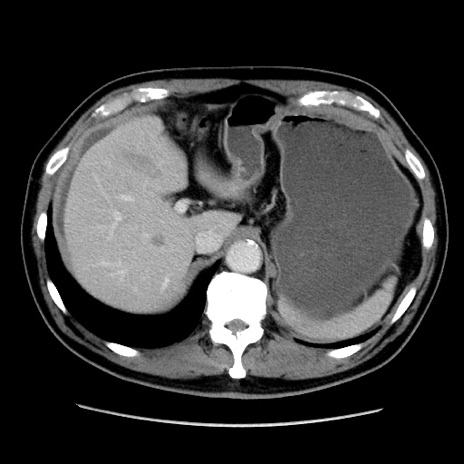

症例16(横断像)

【症例】 70歳代男性

【主訴】 腹痛、嘔吐

【現病歴】 約1ヶ月前より間欠的に腹痛と嘔吐あり、当院消化器内科を受診したところCTで多発する肝臓のLDAを指摘され、精査中であった。以降は消化器症状は安定していたが、2日前より嘔気と腹痛があり、同日より排便・排ガスが消失した。改善認めず、 本日、救急外来を受診した。

【既往歴】 大腸ポリープ切除後。

【身体所見】意識清明・会話良好、BT 36.3℃、BP 127/80mmHg、 P 80bpm、腹部:膨満あり、平坦・軟、上腹部正中および下腹部正中に圧痛あり、反跳痛なし、筋性防御なし。

【データ】WBC 7200、CRP 0.77